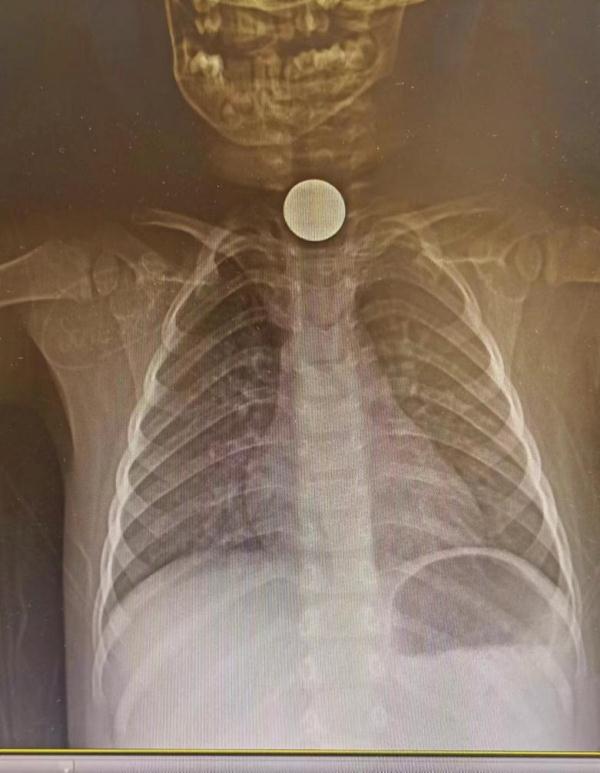

“您好!有个1岁10个月的小女孩吞食了一枚硬币,需在胃镜下取出,请做好准备……”

护士张娜放下电话,又紧急开始准备胃镜异物取出术的所需用物,在消化医学组李佳医师与手术麻醉科赵勇东主任团队的相互协作下,顺利取出一枚一角硬币,术后患儿转入病房,继续观察。